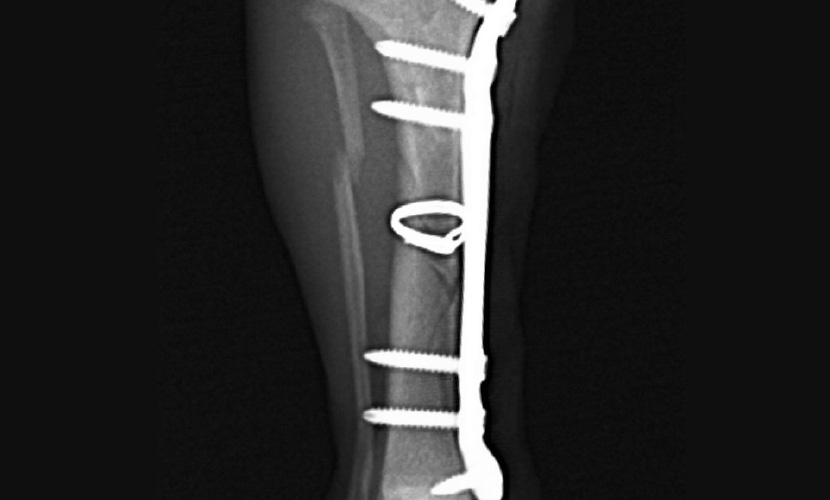

【術後レントゲン画像】

脛骨の解剖学的整復が得られている。両端のスクリューは成長板に干渉しないようモノコーティカル固定とした。